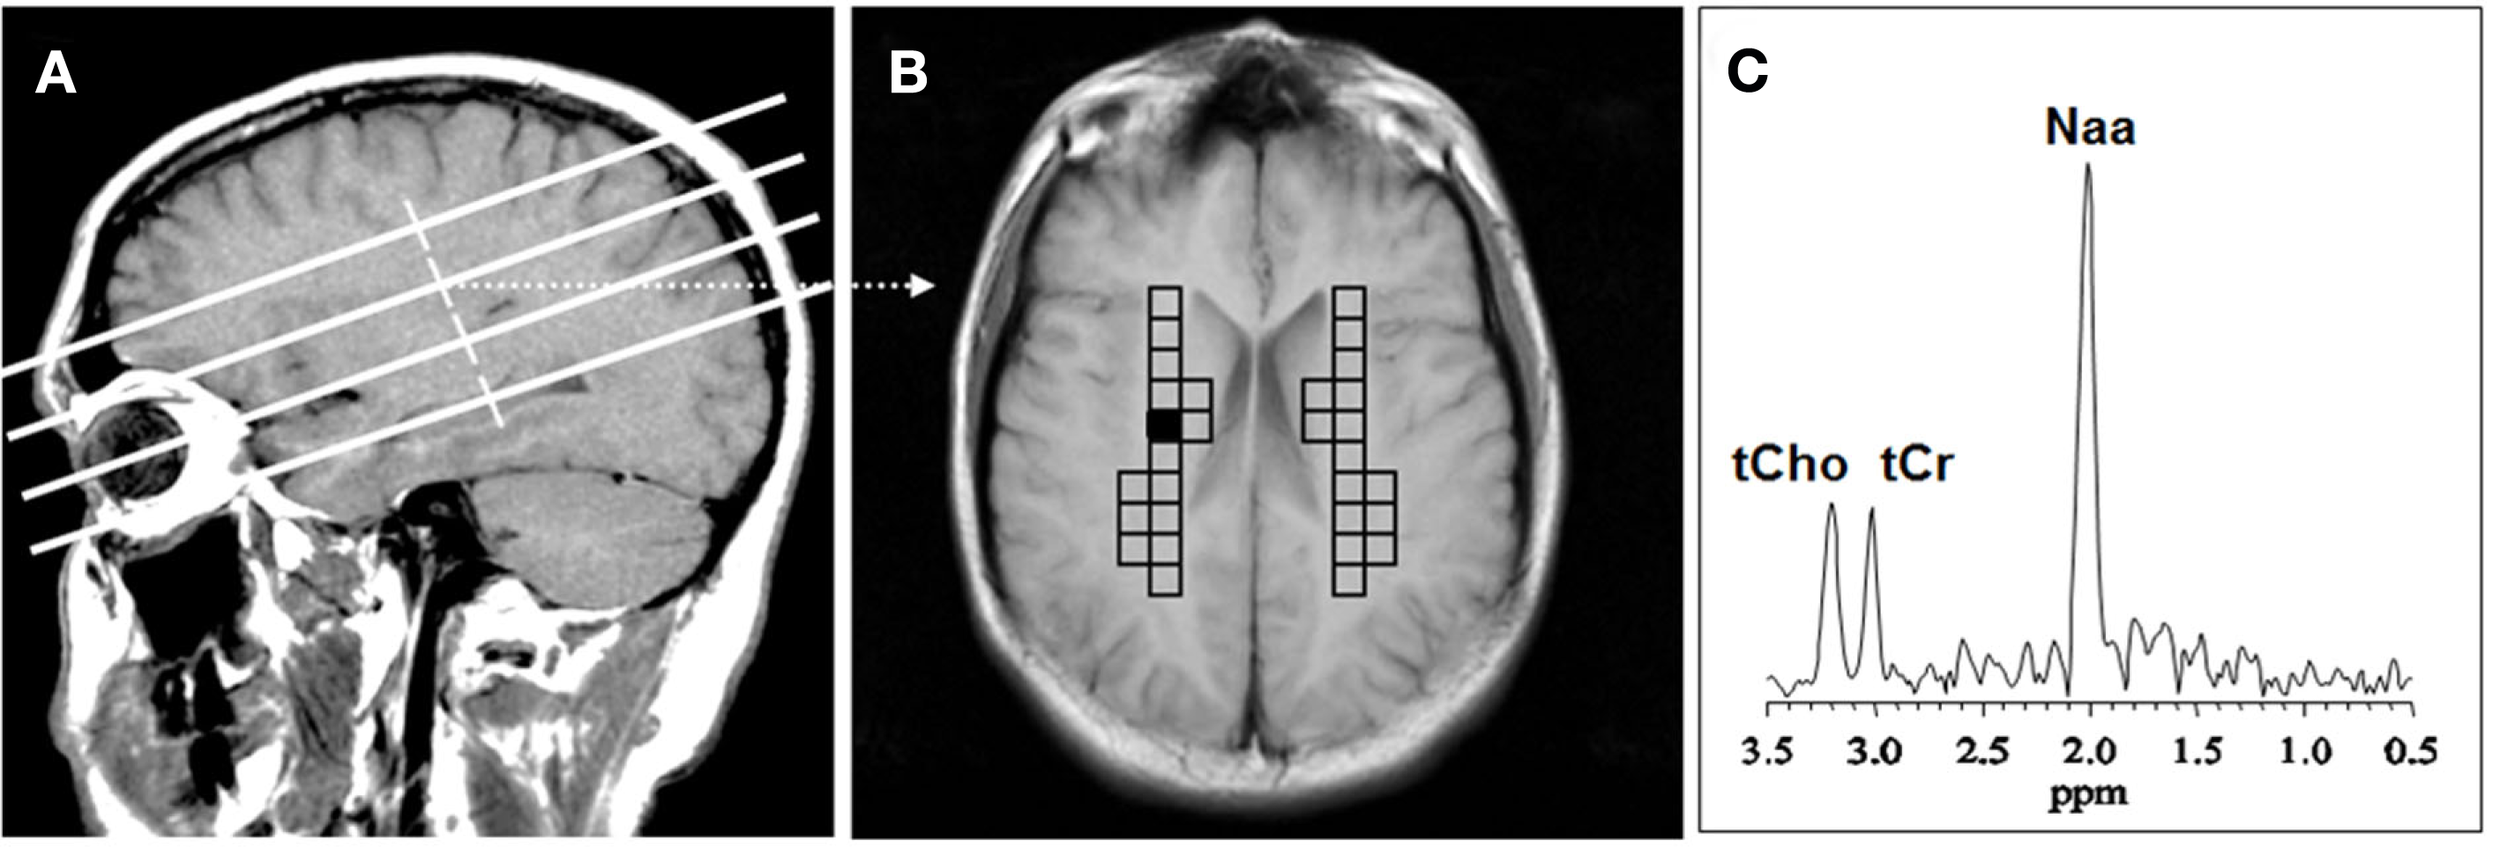

The MRSI data were transferred to an off-line workstation for processing and analysis by two of the study investigators, who used interactive analysis software of their own design. A single researcher blinded to diagnosis selected the ROI’s and performed spectral analysis. Another investigator, Dikoma C. Shungu, who is the senior spectroscopist, ensured that the analyses were performed properly but was not actively involved in ROI selection or data analysis. The raw data were sorted by slice, zero-filled twice along the acquisition domain (to 1024 sampling points), filtered with a Hamming window along spatial domains, and then processed by standard three-dimensional fast Fourier transformation to yield an array of 32 × 32 spectra. The spectral data were automatically corrected for susceptibility shifts due to slight variations in magnetic field strength across the brain using a computer routine that aligned the spectra by maximizing the cross correlation between a spectrum in the data matrix and a representative high SNR reference spectrum selected from the same data matrix. MRSI voxels that best covered the primary ROIs (right and left CSO) in each subject were selected on the basis of voxel location on the matching high-resolution MR localizer images (Figure 1). In each voxel, the CHO metabolite peak area was obtained using a frequency-domain Levenberg–Marquardt non-linear least-squares fitting algorithm. As many pixels as possible were fitted within each ROI and then averaged. Voxels with poor spectral resolution (unresolved CHO peaks at 3.22 ppm) were excluded. The number of voxels rejected varied from subject to subject and did not result in any patient being rejected. The mean of the peak areas for CHO and metabolites within an ROI was computed.

Figure 1. Voxel placement for centrum semiovale (CSO) white matter; (A) MRI depicting the location of the four oblique brain sections investigated; (B) Coronal view from second oblique section overlaid with left and right grids of CSO voxels of interest. (C) MR spectrum from the shaded CSO voxel in the grid shown in (B). NAA, N-acetyl-aspartate; tCho, total choline containing compounds; tCr, total creatine + phosphocreatine.